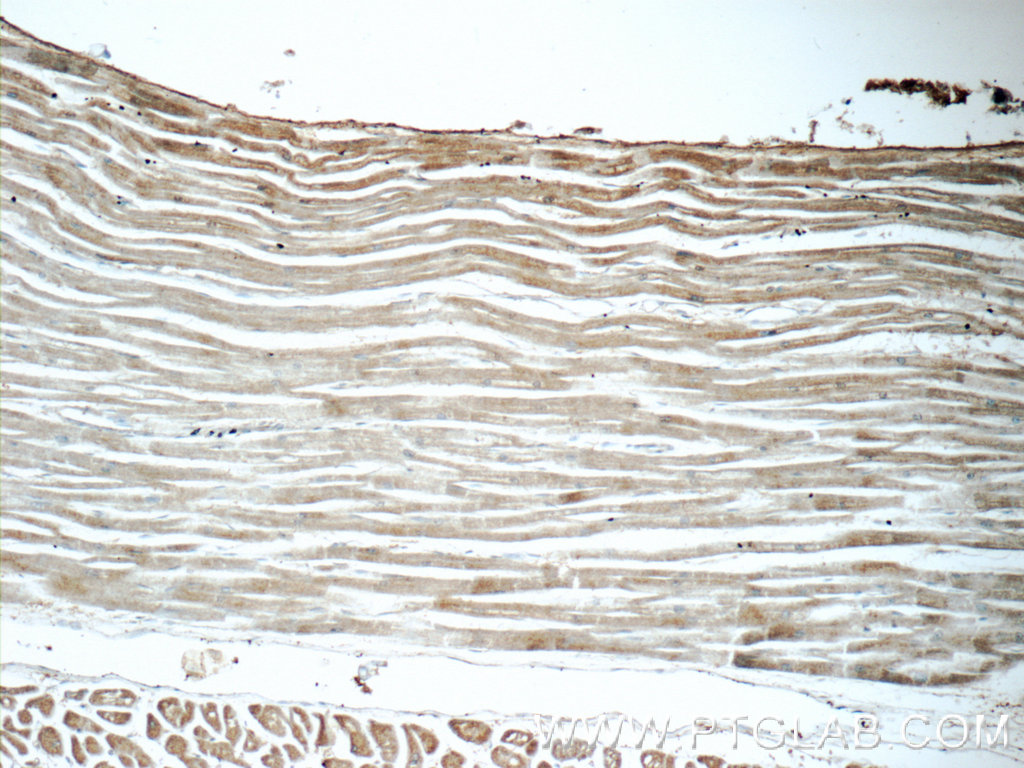

| Positive IHC detected in | human breast cancer tissue, human heart tissue Note: suggested antigen retrieval with TE buffer pH 9.0; (*) Alternatively, antigen retrieval may be performed with citrate buffer pH 6.0 |

| Immunohistochemistry (IHC) | IHC : 1:50-1:500 |